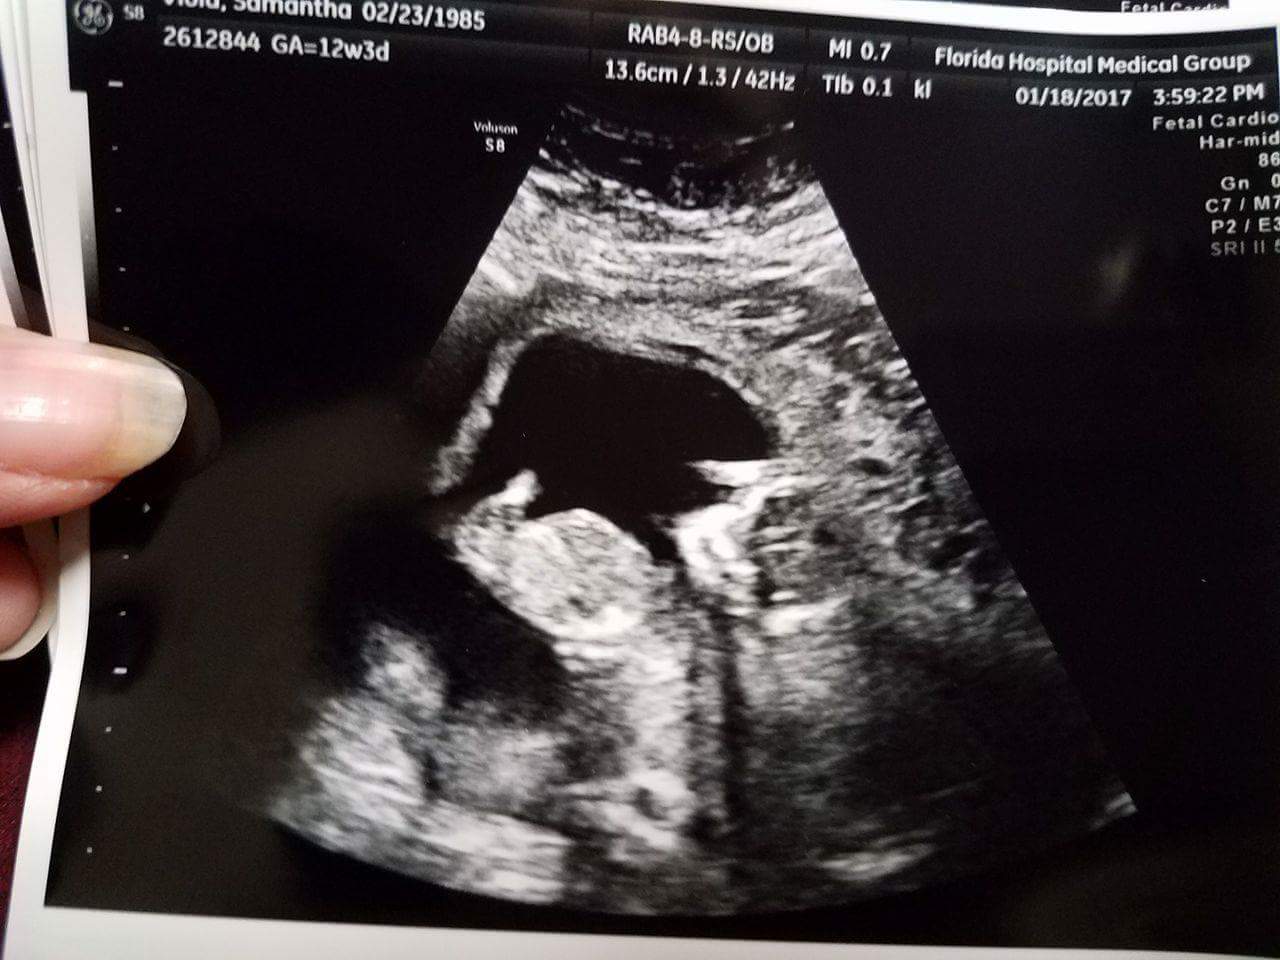

Help! The little one was very wiggly but I'm hoping someone can give me some sort of guess. I was 12w5d I think but they had me measured at 13w5d.